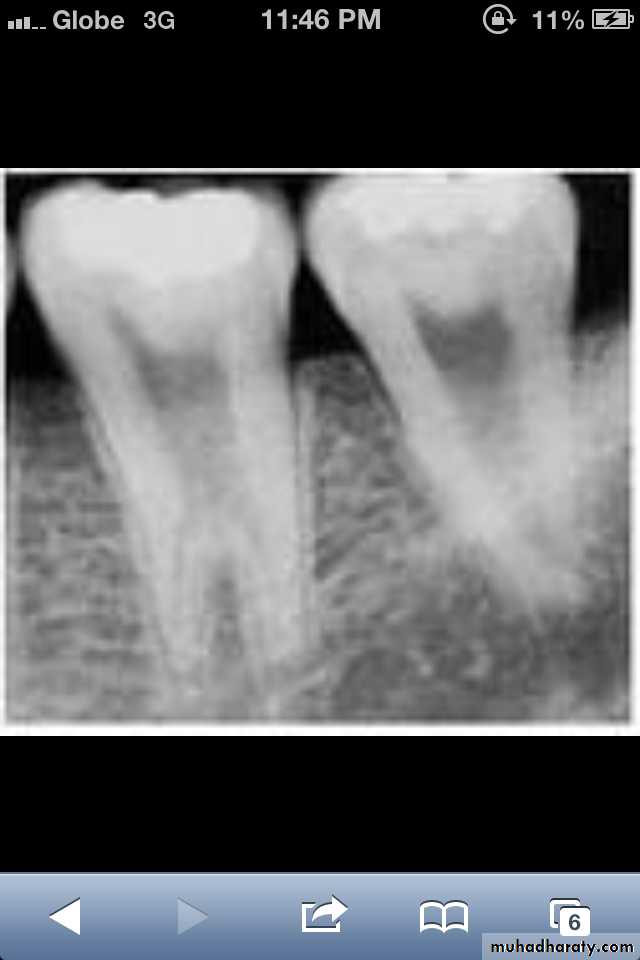

Dentin dysplasia, type II. panoramic &periapical films of the same case show obliteration of the pulp chamber, reduction in the caliber of root canals, and pulp stones obscuring the flame-shaped pulp chambers.

Periapical inflammatory lesions are associated with some of the mandibular anterior teeth.